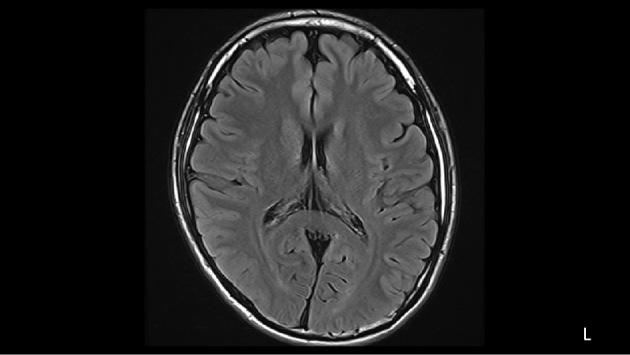

A 20-year-old man with drug-resistant generalized epilepsy (GE) was admitted for video electroencephalography (vEEG) monitoring under treatment with multiple antiepileptic drugs, including levetiracetam (3,000 mg/day), valproic acid (800 mg/day), and lacosamide (LCM) (100 mg/day). No seizures were noted after the withdrawal of levetiracetam. However, after the withdrawal of LCM, atypical absence seizures with a 2- to 2.5-Hz generalized spike and wave complex frequently appeared, followed by subsequent generalized-onset tonic-clonic seizures. After re-administration of LCM, the seizures and epileptic discharges clearly disappeared. Subsequent LCM titration was successful in achieving a seizure-free status. Our vEEG results suggest that LCM may be a worthwhile antiepileptic drug adjunct in refractory GE patients without a risk of worsening absence seizures.

一名 20 岁男性患有耐药性全面性癫痫(GE),在接受多种抗癫痫药物治疗(包括左乙拉西坦[3000mg/天]、丙戊酸[800mg/天]和拉考沙胺[LCM][100mg/天])的情况下入院进行视频脑电图(vEEG)监测。在停用左乙拉西坦后,未出现癫痫发作。然而,在停用 LCM 后,常出现 2-2.5Hz 发作性全面性棘慢波复合波的非典型失神发作,随后出现全面性强直-阵挛性发作。重新给予 LCM 后,癫痫发作和癫痫放电明显消失。随后的 LCM 滴定成功达到无癫痫发作状态。我们的 vEEG 结果表明,LCM 可能是一种有价值的抗癫痫药物辅助治疗药物,用于治疗耐药性全面性癫痫患者,且不会增加失神发作恶化的风险。